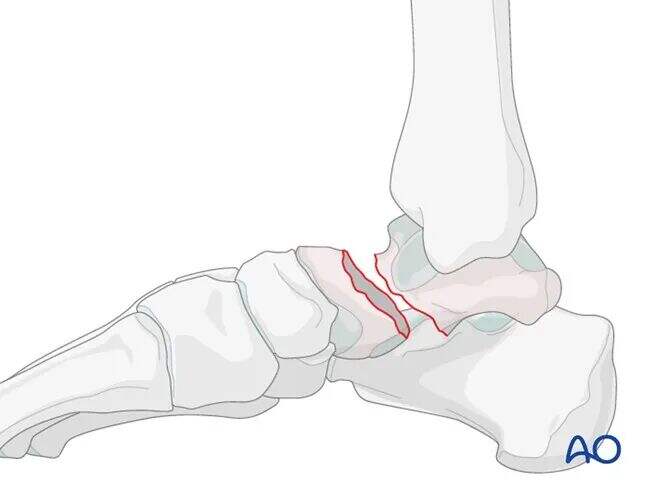

Bočni vrat talusa je običajno nezdrobljen; redukcija se lahko doseže s prepletenjem kostnih fragmentov. Komprezijska vijakna fiksacija je na bočni strani bolj primerna.

Medialni vrat talusa pogosto kaže določeno stopnjo zdrobljenosti. Redukcijo je treba izvesti pod fluoroskopskim vodstvom s C-lokom. Fiksacija naj uporablja popolnoma navojni kortikalni vijak za pozicijsko fiksacijo. Če se uporablja potegni vijak, lahko njegovo pritegnjenje povzroči medialni premik in skrajšanje vrata talusa.

Lateralno ni izgube kosti in je fraktura stabilna zaradi medsebojnega vpenjanja, kar ji omogoča, da prenese tlačna napetost. Optimalna metoda fiksacije je kanalizirani zatezni vijak. Vijak mora potekati skozi kost lateralnega vratu talusa, ne skozi sklepni hrustanec.